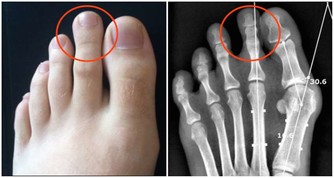

4.鼻炎

秋風起,寶寶噴嚏不止,那是因為秋季較大變化的氣溫導致空氣粉塵風沙增多,寶寶免疫機制還不完善,抵抗力偏弱,容易造成寶寶鼻炎。寶寶鼻炎主要症狀為連續打噴嚏,鼻癢,鼻塞,流清水樣鼻涕,可伴有頭痛。如果不及時控制還會誘發鼻竇炎,腺樣體炎中耳炎,咽炎,支氣管炎,支氣管哮喘,頑固性頭痛等並發症。